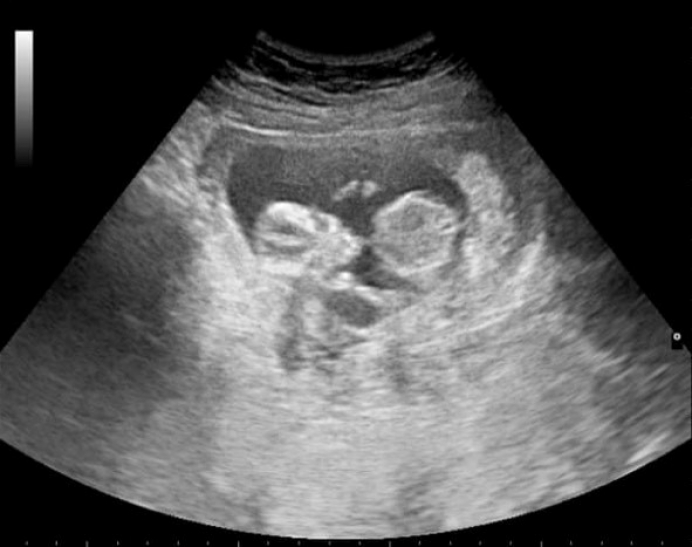

Missouri mom reverses chemical abortion amidst pandemic lockdown, saves unborn baby

Baby rescued via abortion pill reversal celebrates first birthday

“He’s very healthy, very cute.” Pro-life doc rescues baby with Abortion Pill Reversal